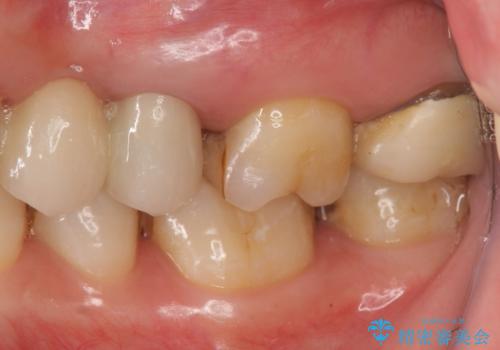

しかし向かい合わせになる歯の咬みこみが強く、インレーでは破折してしまうリスクが高いと予想し、より強固なクラウンで修復することになりました。

向かい合わせの歯の咬みこみが強くインレーよりも強度の高いクラウンでの治療となりました。その中でも色が白くある程度の薄さでも耐久性を発揮するフルジルコニアクラウンでの修復を行いました。適合も良く色調もとてもなじんだため大変喜んでいただけました。